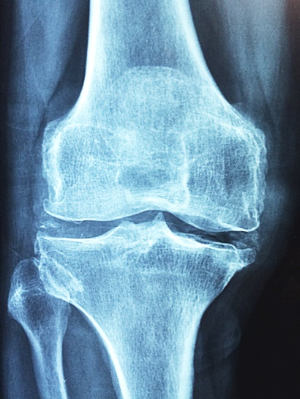

류마티스 관절염은 자가면역 질환으로, 면역 체계가 실수로 정상적인 관절을 공격해 염증과 통증을 일으키고, 관절에 손상을 줄 수 있습니다. 이 질환의 발생 원인은 아직 확실히 밝혀지지 않았지만, 유전적 요인, 감염, 그리고 환경적 요인 등이 복합적으로 작용해 발병 위험을 높일 수 있다고 추정됩니다.

유전적으로는 특정 유전자의 존재가 관절염에 걸릴 가능성을 증가시킬 수 있으며, 가족력이 있는 경우 그 위험은 더 커집니다. 또한, 바이러스나 세균 등의 감염이 면역 반응을 유발하거나, 흡연, 스트레스, 비만, 호르몬 변화와 같은 환경적 요소들도 발병에 영향을 미칠 수 있습니다. 이처럼 다양한 요소들이 류마티스 관절염의 발병에 기여할 수 있으며, 연구를 통해 이를 더욱 명확히 이해하려는 노력이 계속되고 있습니다.